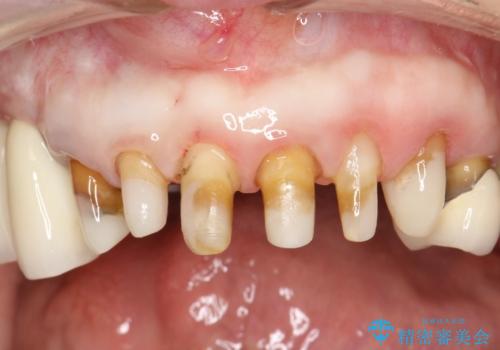

[ 前歯が割れた ] ブリッジによる審美回復治療

![[ 前歯が割れた ] ブリッジによる審美回復治療の症例 治療前](https://seimitsushinbi.jp/wp/wp-content/uploads/2019/11/603d9508dc3fe40b5437057dd45cc165-500x350.jpg?v=1574859330)